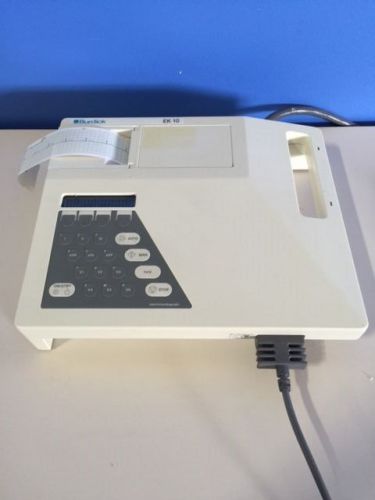

Burdick EK 4 Electrocardiograph with cables

Burdick Spacelabs EK-10 ECG Electrocardiograph. Leads, new battery WARRANTY!